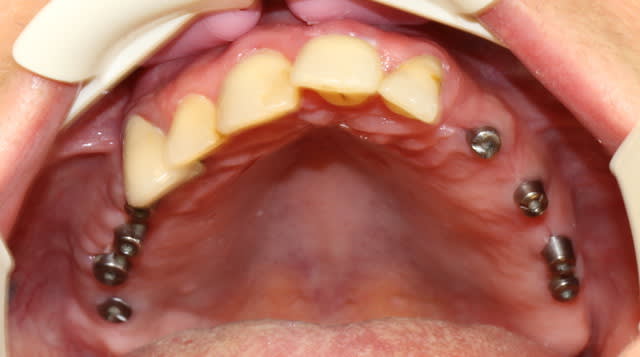

je continue l'entrainement :

voila Marc j'ai recadré!

Le sujet : ajuster un stellite après la pose des vis de cicatrisation sur 8 implants.

Rien de mirifique, juste un "bricolage" pour que la patient puisse manger.